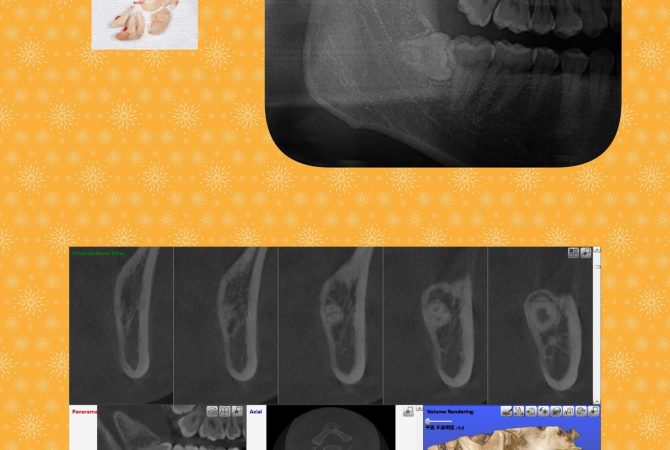

2025.11.15 イベントその他 5歳児健康診査へ行ってきました♪ 詳しく見る 2025.11.14 症例 EMS社エアフローを使用した定期検診症例 詳しく見る 2025.11.12 症例 横向き親知らずの抜歯症例 詳しく見る 2025.10.27 インプラント学び インプラントのための骨造成セミナーを受講 詳しく見る 2025.10.26 イベント院内のこと ハロウィンWeek★キッズイベント開催中 詳しく見る 2025.10.21 学び 博多で歯科麻酔セミナーを受講 詳しく見る 2025.10.19 症例 拡大床と3DLによる小児矯正症例 詳しく見る 2025.10.14 症例 横向き親知らずの抜歯症例 詳しく見る 2025.10.5 治療院内のこと 最新の電動麻酔器を導入♪ 詳しく見る 1 / 29 ページ23…29次へ »